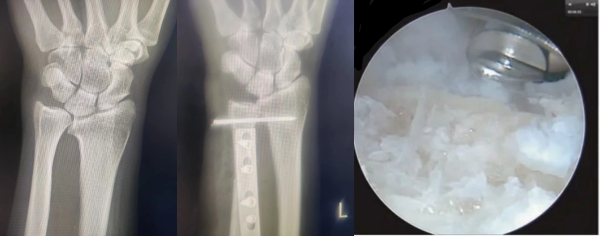

针对成先生的病情,运动医学科党晓谦主任医师、时志斌主任医师、倪建龙副主任医师和宋启春主治医师反复讨论。腕关节镜下的微创腕管松解在二附院已开展十余年,运动医学科已积累了丰富的腕关节镜手术经验。TFCC合并尺骨撞击的手术治疗我们也有多例成功的经验,考虑到开放手术创伤较大,而关节镜手术的创伤更小,出血更少,恢复更快。最终一致决定采用创伤更小、术后康复更快的腕关节镜手术治疗成先生的TFCC损伤。一切准备就绪后,在党晓谦主任医师的指导下、时志斌主任医师主刀,倪建龙副主任医师辅助,手术顺利开展。手术过程中,时志斌主任通过腕关节镜精确地找到了损伤部位,发现患者右侧腕关节中央关节盘退变撕裂,并进行了细致的修复和清理。整个手术过程仅用时20分钟,术中出血少,术后第二天患者疼痛显著减轻,腕关节功能逐步恢复。在短短几天内就能进行简单的腕部活动,预计完全康复后能恢复日常生活和工作。

腕关节镜不仅可以应用于TFCC损伤的清创修复,对于TFCC I A型急性撕裂的患者,在伴有尺骨变异时,同时行尺腕关节减压也有明显疗效。开放手术中的尺骨短缩截骨(USO)是治疗尺骨撞击综合征的最常见手术,常用的截骨方式有横形、斜形、阶梯状截骨。一般选择在尺骨干中远1/3处切除一定长度骨组织,并将截骨端重新固定,虽然能够有效减轻尺骨与腕部骨骼之间的撞击,缓解疼痛、改善功能,但是术中截骨再固定增加了手术时间,术后需要支具固定增加了患者康复锻炼的难度。1992年,Feldon提出了腕关节镜下清创Wafer手术可作为尺骨短缩截骨术的替代性治疗方式。手术主要通过腕关节镜下磨钻切除尺骨小头的极远端部分,保留尺骨茎突,从而降低尺腕关节的纵向压力负荷。一般切除深度为2-4mm。腕关节镜下Wafer手术具有与尺骨截骨短缩术类似的疗效,但是其二次手术比例和发生骨延迟愈合、骨不连的并发症大大减小。